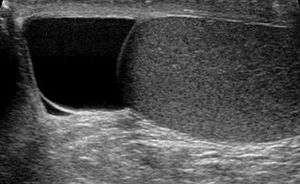

| Ultrasound of a testicle (grey) and a spermatocele (black). | |

Spermatocele (/spɜːrˈmætəsiːl/[1][2]) is a retention cyst of a tubule of the rete testis or the head of the epididymis distended with barely watery fluid that contains spermatozoa. Spermatoceles are the most common cystic condition encountered within the scrotum. They vary in size from several millimeters to many centimeters. Spermatoceles are generally not painful. However, some men may experience discomfort from larger spermatoceles. They are harmless.

Finding a painless, cystic mass at the head of the epididymis, that transilluminates and can be clearly differentiated from the testicle, is generally sufficient. If uncertainty exists, ultrasonography of the scrotum can confirm if it is spermatocele.